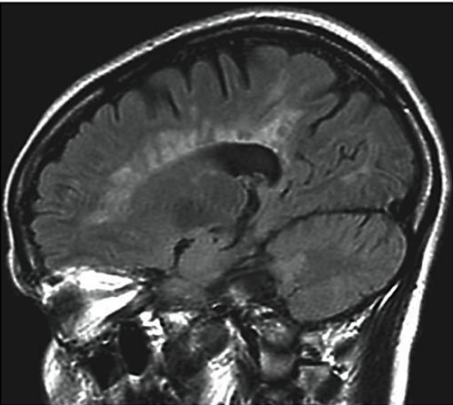

A imagem a seguir corresponde mais provavelmente a:

Enunciado 3339043-1